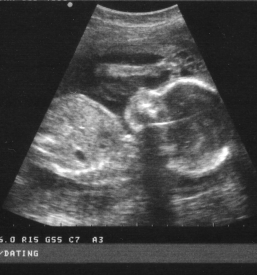

V naši ambulanti se vedno trudimo imeti čimbolj strokoven pristop. To lahko dosežemo le z nenehnim izobraževanjem in spremljanjem razvoja medicinskih postopkov doma ter v tujini. Tako smo se med drugim specializirali za različne preglede, kot je nuhalna svetlina Ptuj.